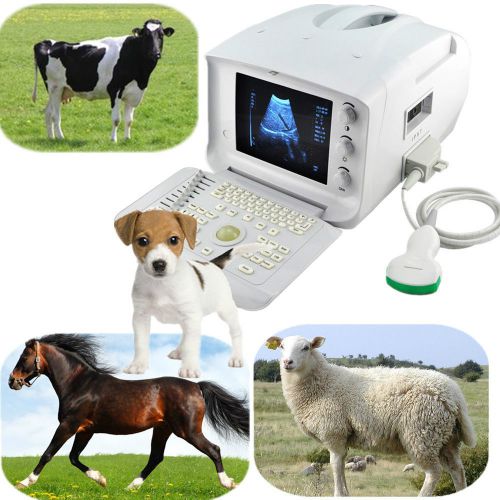

US $1,349.00

Brand | RUS-6000V |

| Probe connectors | 2 | ||

| Model | RUS-6000V | ||

| USB Port | 1 | ||

| MPN | Does not apply | ||

| Video output | PAL-D, VGA | ||

| Country/Region of Manufacture | China | ||

| Net Weight | 10kg | ||

| Standard probe | 5.0MHz micro-convex probe | ||

| Warranty | 18 months | ||

| other options | Linear/Rectal/ convex probe / printer | ||

| Used for | Veterinary Vet Animal |

FDA Veterianry VET Ultrasound Scanner machine + Convex Probe high quality +3D US